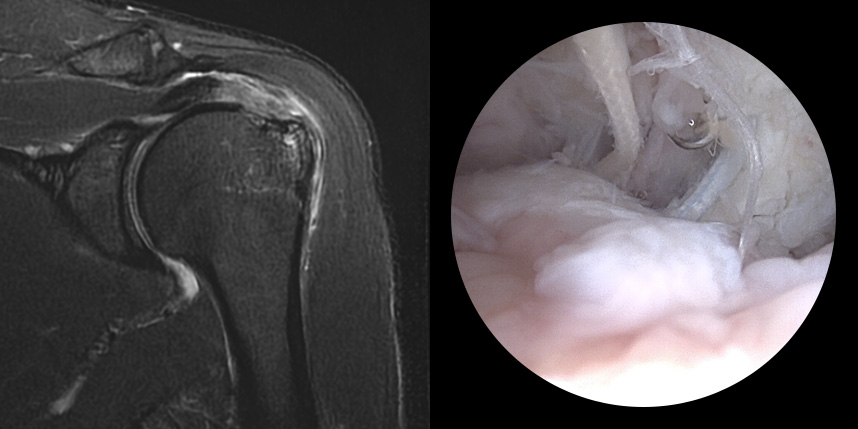

완전 파열시

브릿지 봉합술

접촉면접과 힘줄

부착 압력이 높습니다.

초기,중기,말기 파열에

주로 사용됩니다.

상대적으로

재파열율이 낮습니다.